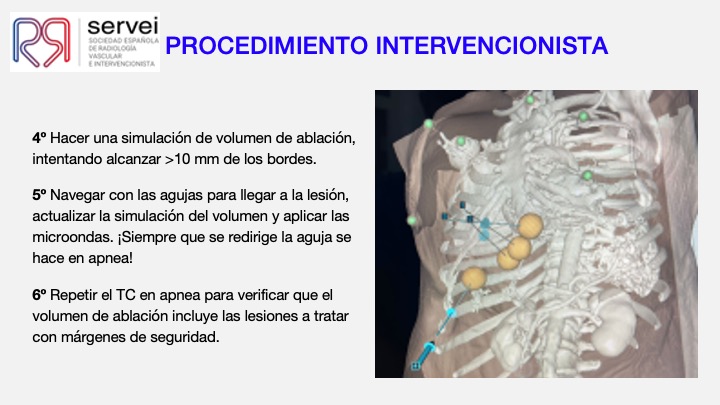

- Ablacion estereoataxia lesiones hepaticas 01

- Ablacion estereoataxia lesiones hepaticas 02

- Ablacion estereoataxia lesiones hepaticas 03

- Ablacion estereoataxia lesiones hepaticas 04

- Ablacion estereoataxia lesiones hepaticas 05

- Ablacion estereoataxia lesiones hepaticas 06

- Ablacion estereoataxia lesiones hepaticas 07

- Ablacion estereoataxia lesiones hepaticas 08

- Ablacion estereoataxia lesiones hepaticas 09

- Ablacion estereoataxia lesiones hepaticas 10

- Ablacion estereoataxia lesiones hepaticas 11

- Ablacion estereoataxia lesiones hepaticas 12

- Ablacion estereoataxia lesiones hepaticas 13

- Ablacion estereoataxia lesiones hepaticas 14